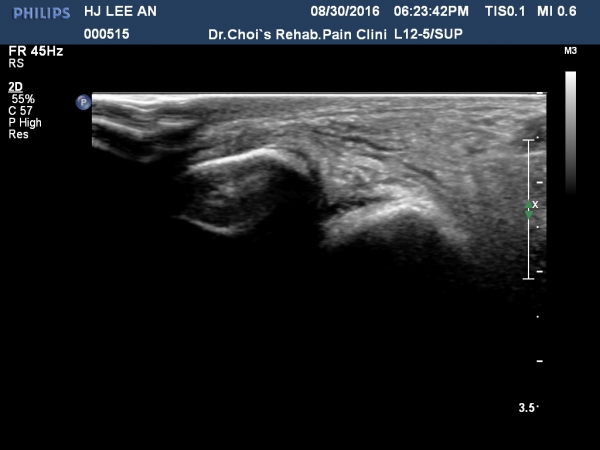

Àü°ÅºñÀδë Á¾´Ü¸é°Ë»ç¿¡¼­ ÀδëÀÇ Àú¿¡ÄÚ ºÎÁ¾ÀÌ °üÂûµÇ³ª °ß¿­°ñÀýÀº °üÂûµÇÁö ¾ÊÀ½(»çÁø 4, 5, 6, 7)

Àü°ÅºñÀδë ÃÊÀ½ÆÄÀ¯µµÇÏ ºÎÇϰ˻翡¼­ ÀδëÀÇ ºñ°ñºÎÂøºÎ¿¡¼­ Àδë¿Í ºÎÂøµÈ °ñÆíÀÇ ÀÌÅ»ÀÌ

°üÂûµÊ(÷ºÎµ¿¿µ»ó).

ÃÊÀ½ÆÄ°Ë»ç¸¦ ½ÃÇàÇϸé Àü°Åºñ Àδë ÀÌ»ó ¿©ºÎÀ» È®ÀÎÇÒ ¼öÀÖÀ¸³ª ÀδëÀÇ ¿ÏÀü ÆÄ¿­¿¡ ÀÇÇÑ

ºñ°ñ°Å°ñ°üÀýÀÇ ºÒ¾ÈÁ¤À̳ª  ÀÌ Áõ·Ê¿Í °°Àº ¹Ì¼¼ÇÑ °ß¿­°ñÀýÀº ÃÊÀ½ÆÄÀ¯µµÇÏ ºÎÇϰ˻縦

½ÃÇàÇÏÁö ¾ÊÀ¸¸é È®ÀÎÇÒ ¼ö ¾ø´Ù.